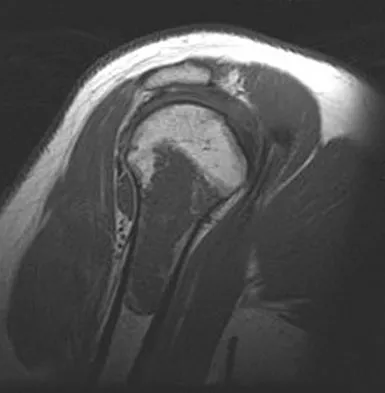

Question 52

Figure 20 shows the MRI scan of a 20-year-old athlete who has a painful shoulder. This pathology is most commonly seen in

Explanation